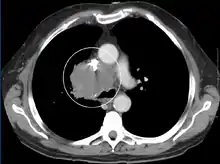

Over 80% of cases are caused by malignant tumors compressing the superior vena cava. Lung cancer, usually small cell carcinoma, comprises 75–80% of these cases and non-Hodgkin lymphoma, most commonly diffuse large B-cell lymphoma, comprises 10–15%. Rare malignant causes include Hodgkin's lymphoma, metastatic cancers, leukemia, leiomyosarcoma of the mediastinal vessels, and plasmocytoma.[3] Syphilis and tuberculosis have also been known to cause superior vena cava syndrome.[5] SVCS can be caused by invasion or compression by a pathological process or by a deep vein thrombosis in the vein itself, although this latter is less common (approximately 35% due to the use of intravascular devices).[5]

The main techniques of diagnosing SVCS are with chest X-rays (CXR), CT scans, transbronchial needle aspiration at bronchoscopy and mediastinoscopy.[6] CXRs often provide the ability to show mediastinal widening and may show the presenting primary cause of SVCS.[6] However, 16% of people with SVC syndrome have a normal chest X-ray. CT scans should be contrast enhanced and be taken on the neck, chest, lower abdomen, and pelvis.[6] They may also show the underlying cause and the extent to which the disease has progressed.[6]